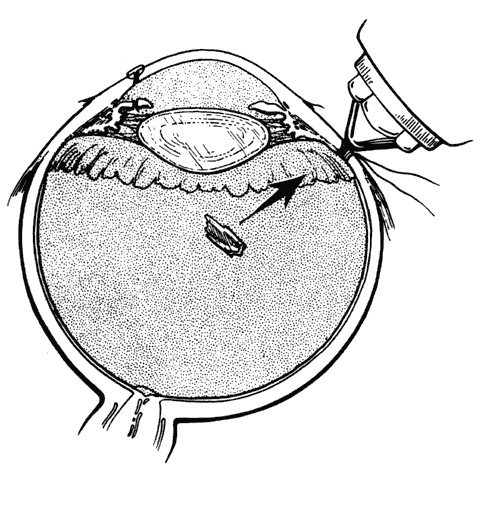

In eyes with clear media, small to medium-sized magnetic IOFBs in the vitreous cavity are removed by an electromagnet through the pars plana after closure of the entrance wound (Fig. 10). A full-thickness scleral incision, down to but not through the pars plana epithelium, is made 3.5 to 4 mm posterior and parallel to the limbus on the side of the globe opposite the IOFB. The length of the incision must permit an unobstructed exit of the foreign object from the eye so that it does not become trapped in the vitreous base. In some cases, the incision is extended anteriorly from its center to form a T-shaped exit wound for relatively large IOFBs. The exposed pars plana epithelium is treated with light diathermy to minimize subsequent hemorrhage and cause slight retraction of the edges of the incision. A nonabsorbable mattress suture is preplaced to permit prompt wound closure after the IOFB is removed, thereby minimizing vitreous loss. The magnet must be aligned with its long axis pointing directly at the foreign body because its power is focused at the base, not the tip, of the conical attachment. Misalignment will attract the IOFB toward tissues adjacent to the sclerotomy. With proper technique, the foreign body rapidly transits the vitreous cavity and works its way through the pars plana epithelium because of the pulsed attractions of the magnet. Failure to exit is usually due to a small incision rather than resistance of the uveal tissue. It is seldom necessary to penetrate the pars plana epithelium with a knife.

Fig. 10. Electromagnetic extraction of small to medium-sized magnetic foreign body. (Sternberg P: Trauma: Principles and techniques of treatment. In Ryan SJ (ed): Retina, Vol 3, p 480. St. Louis, CV Mosby, 1989)

After extraction of the IOFB, the fundus is inspected and retinal breaks, if present, are treated by the methods previously described. With scleral depression, the exit site is visualized. No treatment is applied except in the rare instance where tractional elevation or breaks are detected in the adjacent retina or pars plana epithelium, in which case light cryopexy is used to surround the defects with chorioretinal or cilioretinal adhesions.